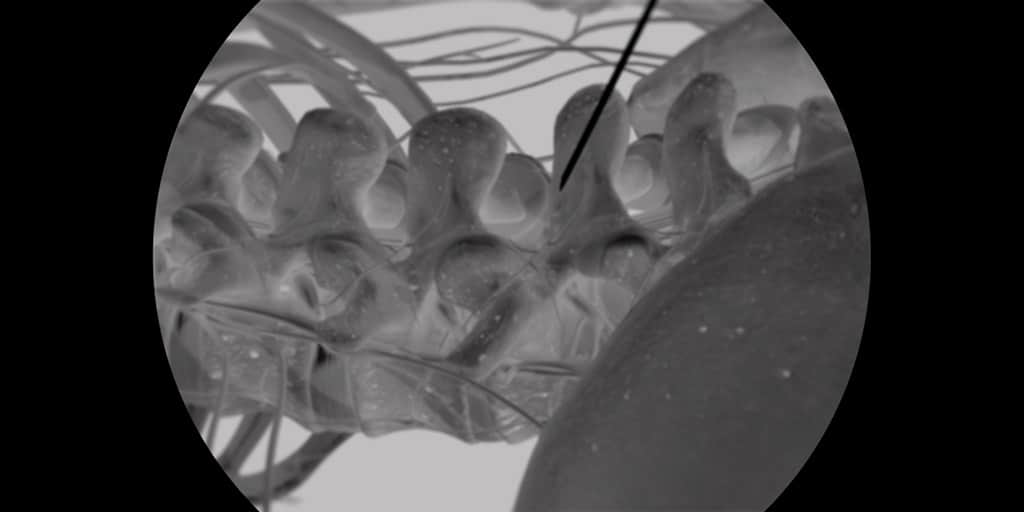

To Advanced Lumbar Bio-Skills Lab που έλαβε χώρα στις 12-13 Οκτωβρίου 2019 στο Άμστερνταμ της Ολλανδίας και διοργανώθηκε υπό την αιγίδα της Spine Intervention Society (SIS) έδωσε τη δυνατότητα στους συμμετέχοντες να διδαχθούν τις πιο προηγμένες και τεκμηριωμένες μικροεπεμβατικές τεχνικές στη σπονδυλική στήλη υπό την καθοδήγηση κορυφαίων εκπαιδευτών της SIS από την Ευρώπη και τις Ηνωμένες Πολιτείες Αμερικής και να εξασκηθούν σε ανατομικά παρασκευάσματα.